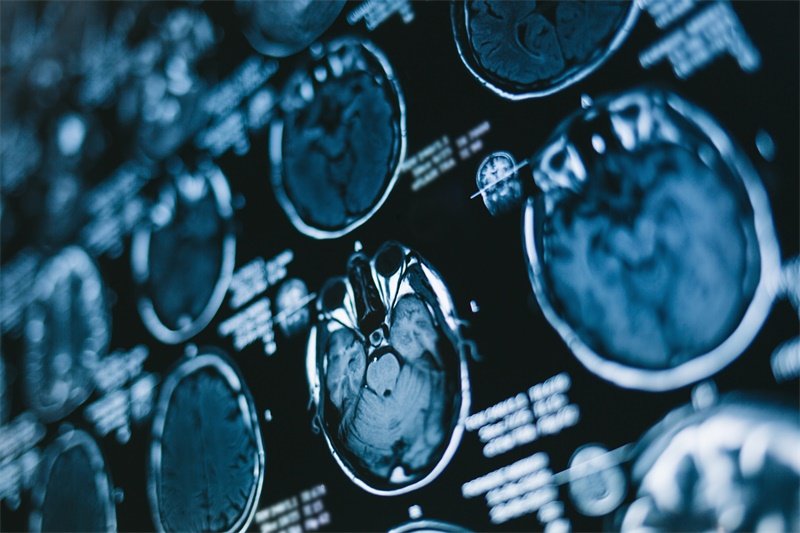

影像学检查是诊断占位性病变的首要手段。磁共振成像(MRI)是最常用的方法,有助于清晰地显示脑组织、肿瘤或囊肿的边界及其对周围结构的影响。另外,计算机断层扫描(CT)也可作为辅助工具,帮助医生分析骨性结构及出血情况。